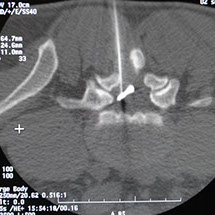

Echo doppler cardiaque Couleur avec technique de strain et doppler tissulaire. Un centre assez complet avec des consultations généralistes et spécialisées, laboratoire, radiologie, échographie et soins. Médecin attaché écho doppler vasculaire.